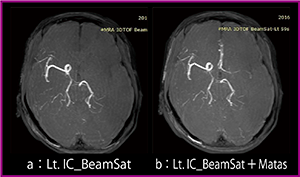

●BeamSatの効果

脳外科手術の術前には,Matas法による検査が行われる。これは術中の脳虚血や脳梗塞を予防するため,患側の頸動脈を指で押さえて対側からのクロスフローがあるかを確認する検査で,血管撮影で行われてきた。この検査をBeamSatで代用可能か検討を行った。

左内頸動脈にBeamSatを印加したMRAでは,左側内頸動脈(左側前大脳動脈,中大脳動脈)および右側前大脳動脈は描出されない(図5 a)。左内頸動脈へのBeamSat印加に加え,左頸動脈を指で押さえると,右側内頸動脈からのクロスフローにより両側前大脳動脈および左側中大脳動脈への血流を認めることができた(図5 b)。

図5 BeamSat+Matasの有無の比較